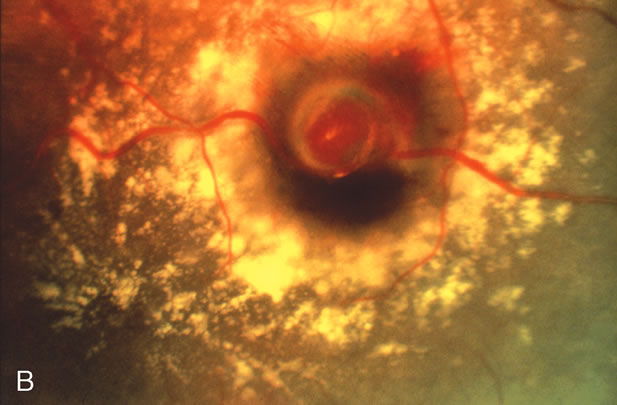

Retinal arterial macroaneurysms usually arise within the first three orders of bifurcation from the optic disc (Fig. 2), often at a point of arteriovenus crossing. Sometimes they occur directly on the optic nerve head3 or on a cilioretinal artery.4 About 20% of affected eyes have multiple aneurysms, and about 10% demonstrate macroaneurysms in both eyes.

Fig. 2. A. Color fundus photograph of a 200-micron macroaneurysm that arises from a retinal artery near the optic disc with thin subretinal hemorrhage that does not threaten the fovea. B. The midphase fluorescein angiogram reveals blockage of choroidal but not retinal vascular hyperfluorescence. C. The late-phase angiogram demonstrates staining of the macroaneurysm.[pa[et[ol0]